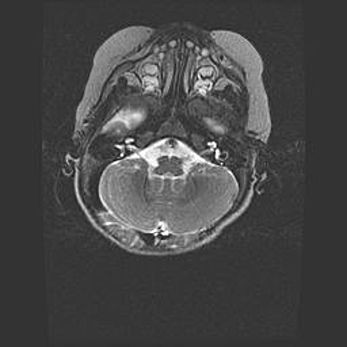

Церебральная ишемия II.

Возраст: 5 дней

Вес: 3400 г

Пол: женский

Окружность головы: 35 см

Срок гестации: 39 недель

Церебральная ишемия – это заболевание, характеризующееся недостаточностью (гипоксией) либо полным прекращением (аноксией) снабжения мозга кислородом по причине закупорки одного или нескольких сосудов. Это приводит к  что метаболическим расстройствам различной степени тяжести в тканях головного мозга, развитию коагуляционных некрозов и гибели нейронов.